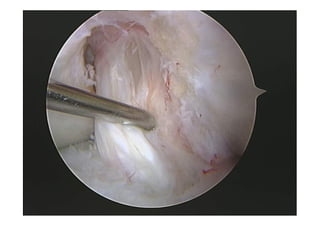

El ojo de la

cerradura